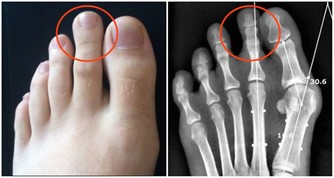

3、睡覺時沒有進入深度睡眠,容易驚醒或發抖,這和睡眠質量有關係,也可能是在生長期的孩子容易發生的狀況,如果不是在生長期就是普通的睡眠問題,但是也不排除是缺鈣導致的肌肉抽搐,偶爾發生沒有關係,如果頻繁發作就該去醫院諮詢一下,吃一些安神和補鈣的藥物。

4、考慮可能與缺鈣和勞累有關係的,建議注意休息。適當補充鈣,建議口服蓋爾奇d試試。多吃骨頭湯和鯽魚湯瘦肉,多喝牛奶是補充鈣劑最安全有效的途徑。牛奶中鈣的含量很豐富,每百克牛奶中含鈣可達100~110毫克,而且這種鈣為天然乳鈣,容易被人體消化吸收。況且,藥補不如食補。